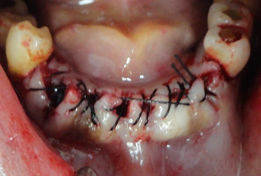

Os alvéolos, preservados, durante as extrações, foram preenchidos com Hemospon (Esponja Hemostática de Colágeno Hidrolisado (Gelatina) liofilizada). Suturados firmemente, espera- de 15 a 30 minutos para que a gelatina do Hemospon, induza a formação de fibrina, formando o coágulo, no defeito ósseo. Que através de histodiferenciações celulares, que descreveremos, induzirá a formação óssea.

O paciente não sairia desdentado do consultório, por este motivo, em todos os casos confeccionamos uma PPR, ao final da cirurgia. EXTRAÇÂO DE DENTES CONDENADOS NA ÀREA DE MOLARES SUPERIORES E RELIZAÇÃO DE ROG. Importante saber da necessidade e a importância da RTG (Regeneração Tecidual Guiada), ou em implantodontia a ROG (Regeneração Óssea Guiada), nos momentos das extrações dentárias, com vista a recuperação dos tecidos.